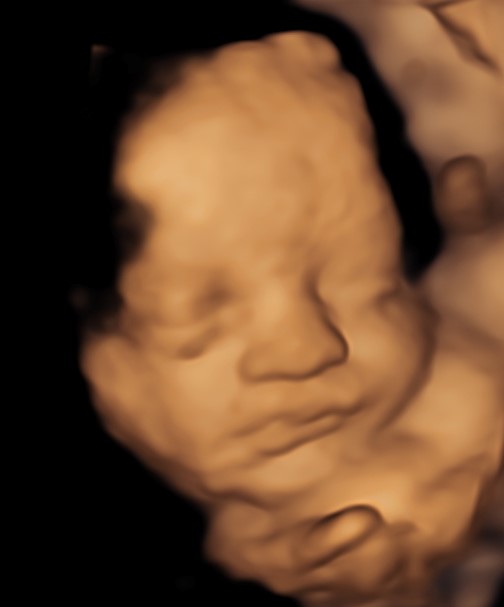

4D/5D/HD Ultrasound Gallery

Gallery